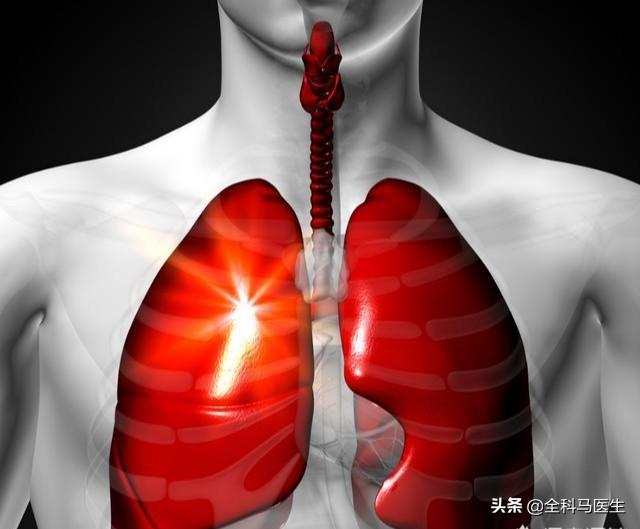

IV. douleur thoracique

Environ 50 % des patients atteints d'un cancer du poumon souffriront de douleurs thoraciques. Au stade précoce du cancer du poumon, ces douleurs thoraciques seront intermittentes et aggravées par la toux, la respiration profonde ou un changement de position du corps.

: : ④ Douleur thoracique

Au stade précoce du cancer du poumon, la douleur thoracique n'apparaît généralement pas, mais lorsque le cancer du poumon évolue vers un stade moyen ou avancé, la tumeur continuant à croître, il est facile d'exercer une pression sur les nerfs, ce qui provoque une douleur vague ou sourde dans la poitrine, et parfois cette douleur irradie même vers l'arrière de la poitrine ou l'arrière de l'épaule, provoquant ainsi des douleurs dorsales. En outre, les tissus normaux des poumons sont constamment endommagés par les cellules cancéreuses, ce qui provoque également une vague douleur dans la poitrine. Si la douleur dans la poitrine est plus intense, si elle est si douloureuse que l'on ne peut pas dormir la nuit et si elle est insupportable pendant la journée, il est très probable que le cancer du poumon ait déjà atteint un stade avancé.